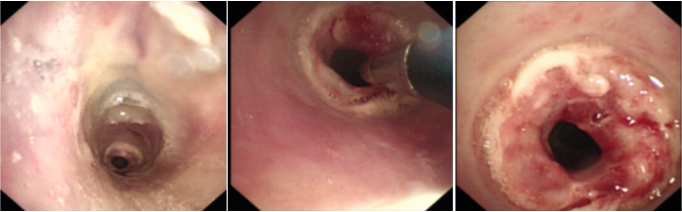

病例4危重的双肺间质疾病

患者,男性,48岁,咳嗽、气短2个月,加重4天。血气分析:pH 7.46,PaO2 61 mmHg,PaCO2 24 mmHg。外院病原学提示肺孢子菌及耐甲氧西林葡萄球菌。胸部CT提示感染(图17)

图片

图17  患者胸部CT

无创呼吸机三通面罩(FiO2 70%)下行床旁纤维支气管镜检查:双侧支气管黏膜充血,右中间支气管见小片状伪膜,管腔通畅,未见肿物、出血及狭窄;肺泡灌洗液送结核、细菌、真菌培养、NGS及GM试验;于伪膜处、左肺下叶刷片送细菌、真菌及病理检查;行TBLB(左肺下叶外、后基底段及左肺上叶舌段)送病理检查,结果提示(左肺上叶舌段)黏膜低分化腺癌浸润。

思考此例患者时间较早,在无创机械通气下完成了肺活检,为明确诊断争取了时机。②为间质性肺疾病提供了新的诊断思路。